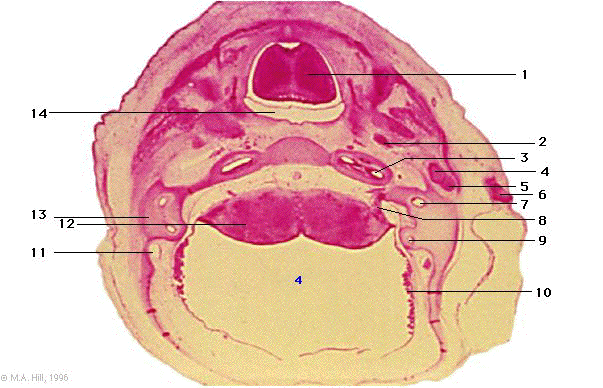

1 |

dorsum of tongue |

2 |

internal carotid artery |

3 |

cochlea |

4 |

malleus |

5 |

incus |

6 |

precartilage of auricle |

7 |

ampulla |

8 |

VII and VIII nerve |

9 |

semicircular canal |

10 |

choroid plexus |

11 |

sigmoid sinus |

12 |

pons |

13 |

temporal cartilage |

14 |

oropharynx communicating with nasopharynx |